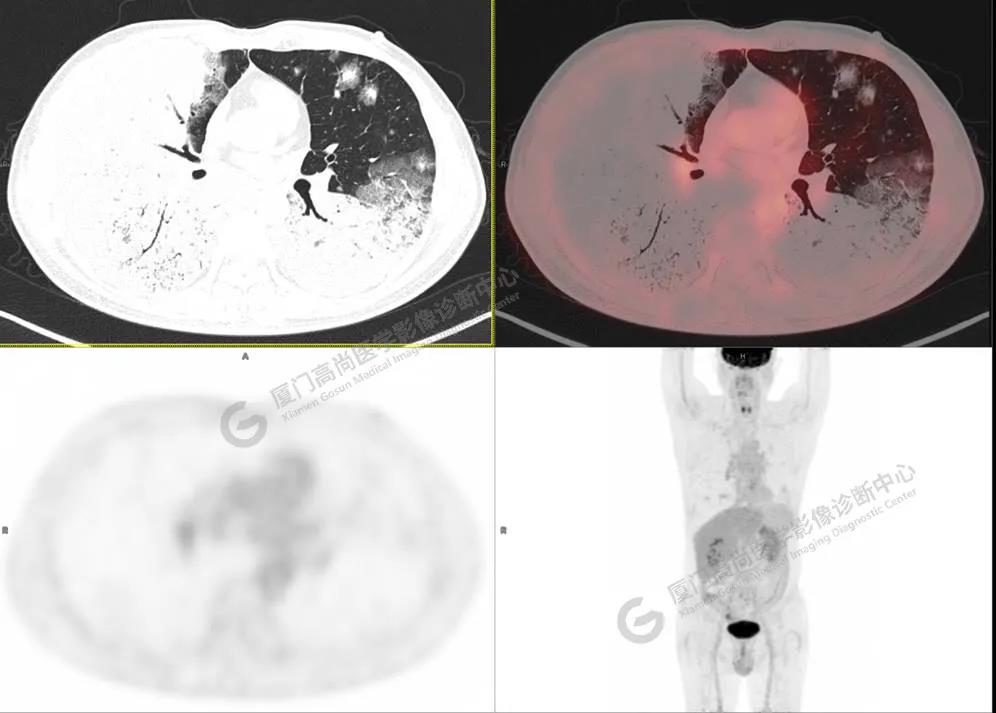

PET/CT影像圖

圖2

PET/CT所見(jiàn):雙肺大片實(shí)變影及磨玻璃影,部分呈地圖樣改變,累及右肺尖,部分放射性攝取輕微增高,SUVmax 1.77,其內(nèi)見(jiàn)多發(fā)支氣管充氣征象。

影像診斷: 雙肺大片實(shí)變影及磨玻璃影,大部分代謝不高,局部代謝輕微增高,考慮肺泡蛋白沉積癥,建議病理學(xué)檢查或肺泡灌洗物檢查。